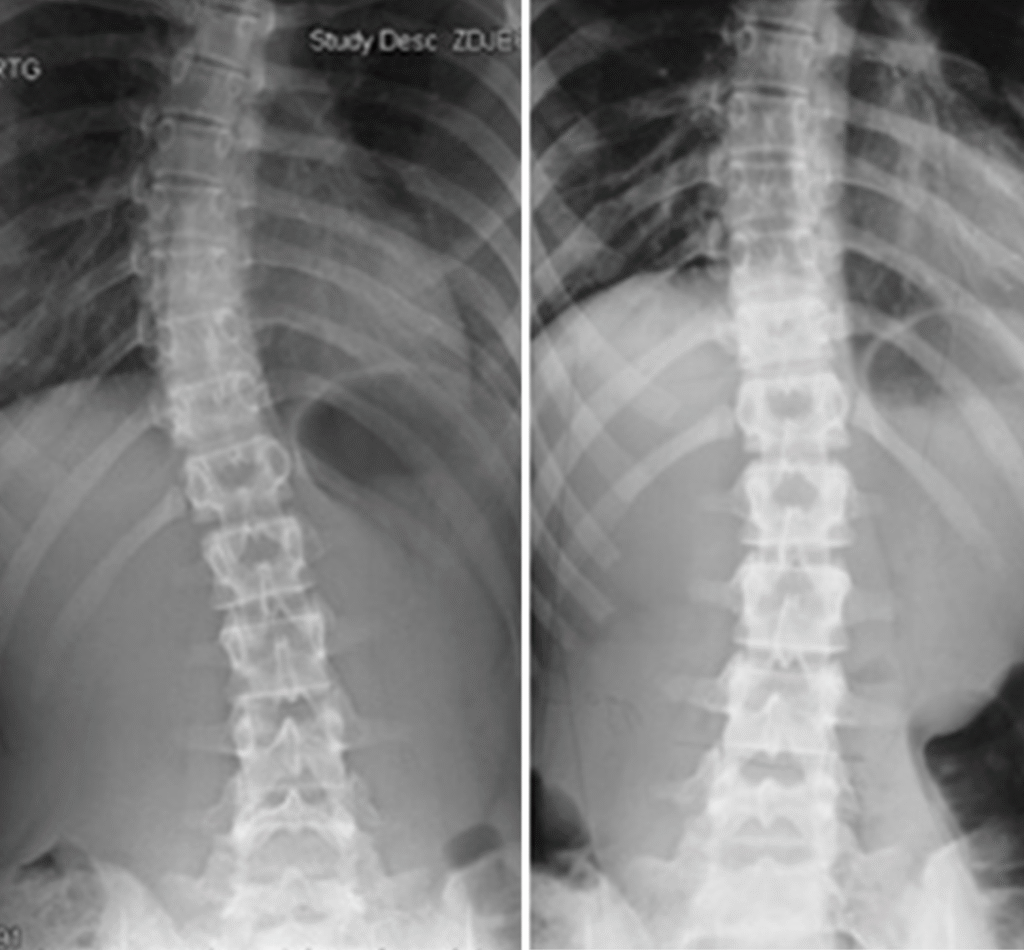

Dawid – 7 lat

Skolioza jednołukowa (statyczna) – zdj. z lewej. Korekcja uzyskana w trakcie jednej wizyty – zdj. z prawej